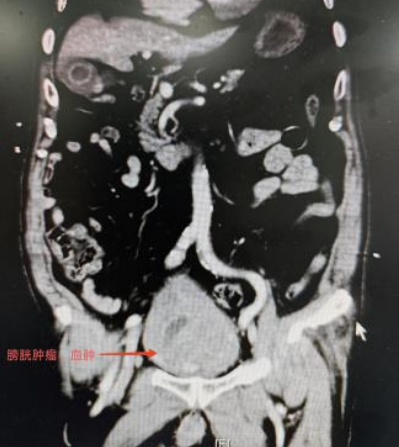

泌尿外科一区主任傅发军介绍,患者确诊为晚期膀胱癌,肿瘤体积大、浸润深,且合并高血压、冠心病、脑梗死等多种基础疾病。“就像体内埋着定时炸弹,肿瘤不断侵蚀血管,保守治疗已无法控制致命性出血。”

“对于晚期膀胱癌反复出血病例,根治手术是唯一能确定性止血的治疗方式。”傅发军解释。术中,专家团队采用微创技术精准分离,完整切除肿瘤,同时行输尿管皮肤造口。手术历时3小时顺利完成,出血量控制在200毫升以内。